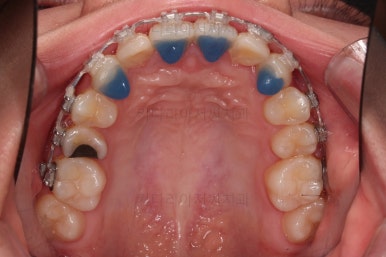

장치를 처음 부착한 사진입니다.

이번 환자분은 특징적으로 윗니의 장치와 아랫니의 장치가 다르죠.

윗니는 좀 더 심미적인 세라믹으로 선택하셨고 아랫니는 비교적 저렴하고 부피가 약간 작고 튼튼한 메탈로 진행했습니다.

비교적 조기에 앞니는 가지런해졌고요.

대신 교합이나 기울어진 느낌 등 디테일을 맞추기 위한 작업을 추후에 계속 하게 됩니다.